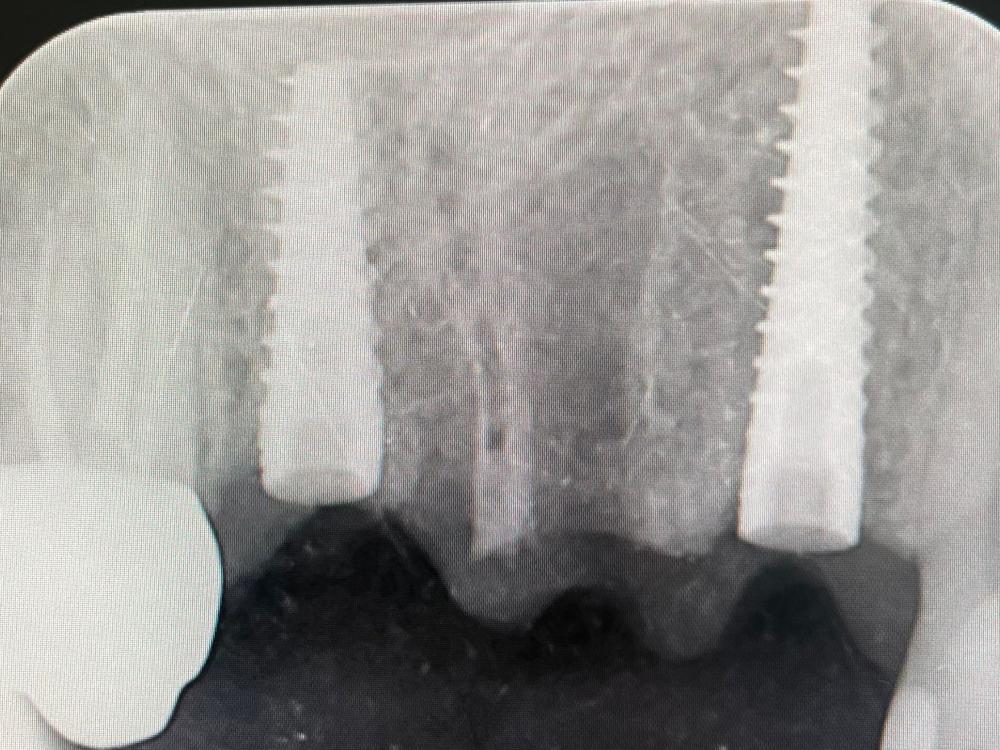

Presso lo Studio Dentistico Zambon siamo specializzati in trattamenti avanzati come il postestrattivo con carico immediato, un intervento innovativo che consente di sostituire i denti mancanti in modo rapido e sicuro, riducendo notevolmente il tempo di guarigione e il disagio per il paziente.

Grazie all’utilizzo della chirurgia guidata, siamo in grado di pianificare e realizzare impianti dentali con precisione, assicurando risultati eccellenti e duraturi.

Il trattamento postestrattivo con carico immediato è un protocollo che permette di inserire un impianto dentale subito dopo l’estrazione del dente naturale, evitando lunghi tempi di attesa tra l’estrazione e l’inserimento del nuovo dente. Questa soluzione si dimostra ideale per chi desidera ripristinare il sorriso e la funzionalità dei denti in tempi ridotti, evitando multiple sedute e massimizzando il comfort.

La chirurgia guidata è una tecnica avanzata che si avvale di tecnologie digitali per pianificare e simulare l’intervento in modo personalizzato. Con una scansione digitale 3D della bocca, il nostro team può posizionare gli impianti con estrema precisione, seguendo un percorso predefinito che riduce il margine d'errore. Questo approccio, unito al trattamento postestrattivo con carico immediato, offre diversi vantaggi: